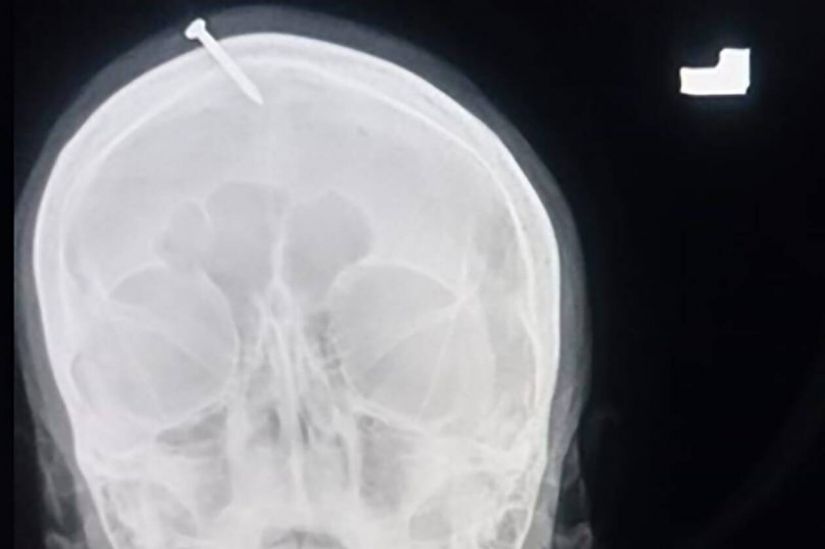

Αδιανόητα πράγματα έλαβαν χώρα στο Πακιστάν, εκεί που μια έγκυος έπεσε θύμα δοξασιών, καθώς της κάρφωσαν ένα καρφί 5 εκατοστών στο κεφάλι της για να σιγουρευτούν ότι θα κάνει αγόρι!

Η οικογένεια της γυναίκας την οδήγησε σε έναν τοπικό σαμάνο, για να σιγουρευτούν για το φύλο του μωρού και εκείνος τους εγγυήθηκε επιτυχία στην ευχή τους μόνο αν κάρφωναν έναν καρφί στο κεφάλι της εγκυμονούσας.

Αμέσως μετά την σοκαριστική τελετή, η γυναίκα οδηγήθηκε στο νοσοκομείο της πόλης Peshawar, όπου οι γιατροί άκουσαν έκπληκτοι τι είχε συμβεί αφαιρώντας λίγο αργότερα το καρφί της γυναίκας από το μέτωπό της.

Αξίζει να σημειωθεί πως αρχικά η γυναίκα έλεγε στους γιατρούς πως το έκανε μόνη της, ωστόσο λίγο αργότερα παραδέχτηκε την αλήθεια.

Σύμφωνα με τον γιατρό, Haider Khan, το καρφί δεν έφτασε στον εγκέφαλο της γυναίκας ωστόσο ο πόνος ήταν αφόρητος…